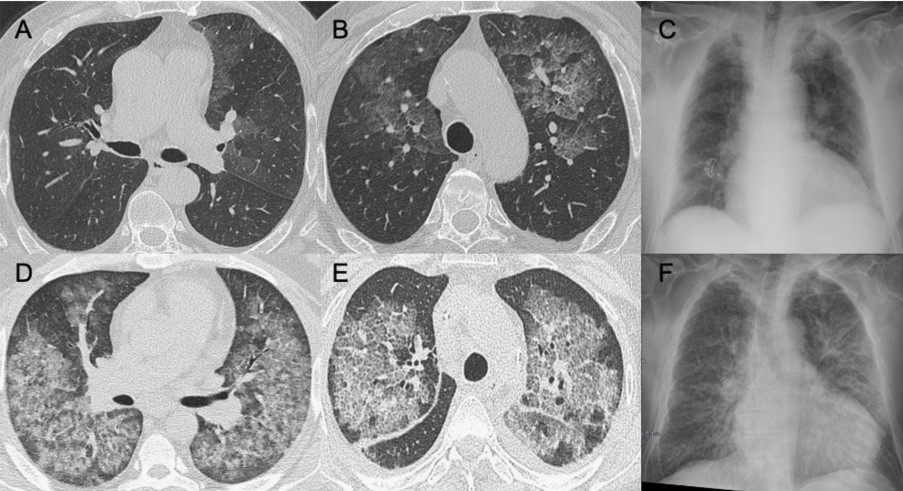

● CXR:雙側(cè)和多灶性GGO,可表現(xiàn)為肺葉或節(jié)段性分布,與細(xì)菌性肺炎相似。出現(xiàn)并發(fā)癥時(shí),單側(cè)肺透亮過(guò)度和呼氣時(shí)空氣滯留(Swyer–James綜合征)。

● CT:雙側(cè)和多灶性GGO,可表現(xiàn)為肺葉或節(jié)段性分布,與細(xì)菌性肺炎相似。

圖5 腺病毒肺炎和Swyer–James綜合征。圖(A)顯示了一例急性腺病毒肺炎,具有典型的多灶性和大葉GGO,與細(xì)菌性肺炎相似。圖(B,C)顯示其導(dǎo)致的長(zhǎng)期后遺癥——Swyer–James綜合征的表現(xiàn)。

?巨細(xì)胞病毒

● CXR:彌漫性和雙側(cè)實(shí)變伴間質(zhì)受累。

● CT:間質(zhì)和肺泡浸潤(rùn),雙側(cè)和不對(duì)稱性GGO區(qū)域,與實(shí)質(zhì)實(shí)變區(qū)域相關(guān)。

圖8 巨細(xì)胞病毒性肺炎。圖(A–C)顯示其輕度實(shí)質(zhì)受累的情況。圖(D、E)顯示患者有彌漫性GGO和鋪路石征,胸片(F)中同樣可見(jiàn)。